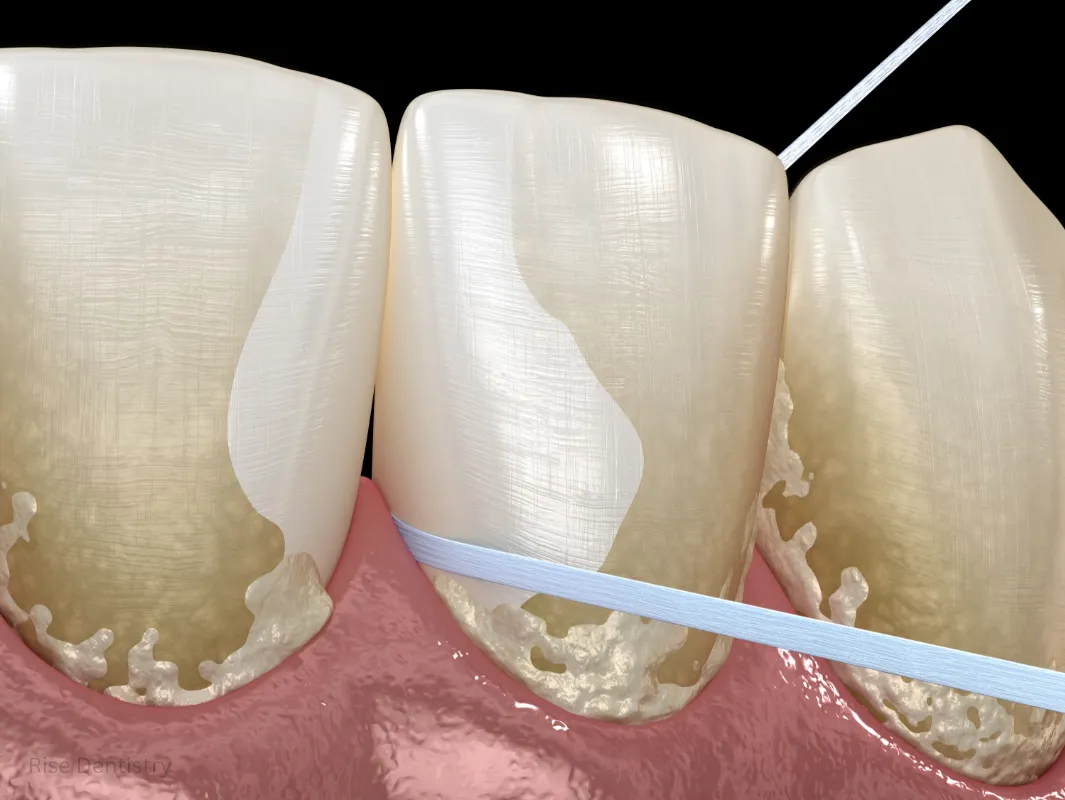

Root Planing – Smoothing Teeth Roots

In periodontal scaling and root planing, the roots are polished to help gums reattach securely and heal faster.